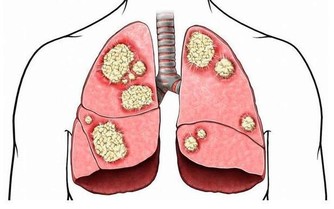

有助於保護細胞免受自由基的侵害,這甚至可以幫助我們預防心血管疾病和癌症。